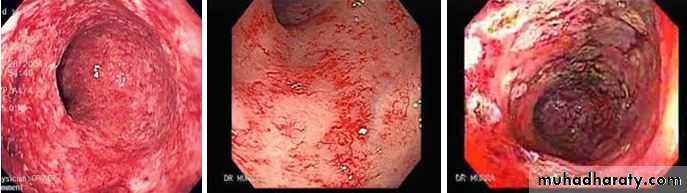

-Acute injury: nausea, vomiting , abdominal pain and diarrhea . When the rectum and colon are involved, rectal mucus, bleeding and tenesmus occur. rectal changes at sigmoidoscopy resemble ulcerative proctitis or ulcerative colitis. Barium follow-through showing small bowel strictures, ulcers and fistulae

-Chronic Phase :Proctocolitis , Bleeding from telangiectasia, Small bowel strictures, Fistulae: rectovaginal , colovesical , enterocolic ; Adhesions, Malabsorption: bacterial overgrowth, bile salt malabsorption(ileal damage).